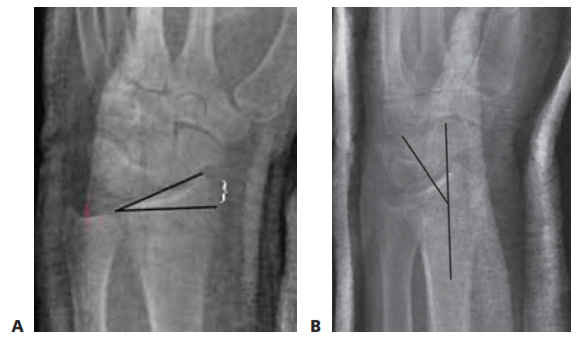

Normal radiographic osseous parameters of the distal radius are critical benchmarks for surgical restoration. The articular surface normally exhibits a volar tilt averaging 10 degrees (range 2 to 20 degrees). Radial height, measured from the tip of the radial styloid to the ulnar articular surface, averages 11 mm. Radial inclination, measured in the coronal plane, averages 22 degrees. Ulnar variance, defining the relative length of the radius to the ulnar head at the sigmoid notch, is highly variable and patient-dependent but must be restored to its pre-injury state to prevent ulnocarpal impaction or distal radioulnar joint incongruity.

Thorough preoperative planning is essential for successful surgical execution. Standard radiographic evaluation must include posteroanterior, true lateral, and oblique views of the wrist. The true lateral view is critical for assessing volar tilt and dorsal comminution, while the posteroanterior view evaluates radial height, inclination, and ulnar variance.